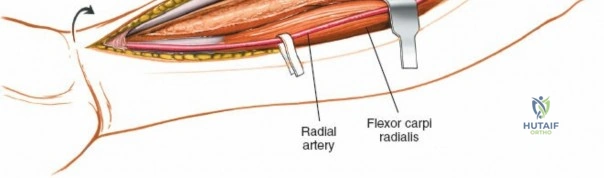

To confirm the correct plane, look for the superficial branch of the radial nerve. This sensory nerve runs on the undersurface of the brachioradialis muscle. Once the true medial edge of the brachioradialis is found, develop the plane between it and the pronator teres (proximally) or the flexor carpi radialis (distally). Retract the brachioradialis laterally, taking care to keep the superficial radial nerve attached to its undersurface to protect it from traction injury.

Managing the Radial Artery and Recurrent Leash

As the brachioradialis is retracted laterally, the radial artery and its venae comitantes are exposed lying deep in the middle part of the forearm, closely related to the medial edge of the wound. Begin dissection distally and work proximally. Just below the elbow joint, the radial artery gives off the recurrent radial artery and a leash of muscular branches that dive laterally into the brachioradialis.

This leash must be meticulously managed. Take time to isolate, ligate, and divide these vessels. Do not attempt to use electrocautery alone on the larger branches, and absolutely avoid blunt avulsion. Avulsion of these vessels from the main radial artery is a potent cause of difficult-to-control intraoperative bleeding and severe postoperative hematoma. Once the leash is divided, the brachioradialis can be fully mobilized laterally, exposing the deep muscular layer.